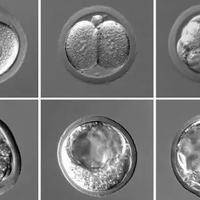

嘿,大家好!今天咱们聊聊辅助生殖技术里一个挺热门的话题——单个5天囊胚移植。说实话,对很多希望通过试管婴儿实现父母梦的家庭来说,这可不是个简单决定。我自己呢,也曾经历过这个过程,所以想分享一些个人观点和实际案例,帮你更好地理解这事儿。什么是5天囊胚移植?首先,得明白囊胚移植是咋回事。在试管婴儿流程中,卵子和精子在实验室结合后,会发育成胚胎。一般来说,胚胎在体外培养到第三天,就叫早期胚胎,但有些医生

嘿,朋友!如果你正在了解或考虑三代试管婴儿技术,那你肯定听过“囊胚等级”这个词儿。简单来说,三代试管就是在胚胎植入前进行遗传学诊断,确保宝宝健康的技术。而囊胚呢,是胚胎发育到第五六天的一个关键阶段,像个小气球一样,里面包着将来变成宝宝的细胞。这时候,医生们会给囊胚打分,也就是评定等级,这直接关系到试管婴儿的成功率。想想看,等级高的囊胚,植入后更可能顺利着床,帮你圆梦。所以,今天咱们就来聊聊,三代试